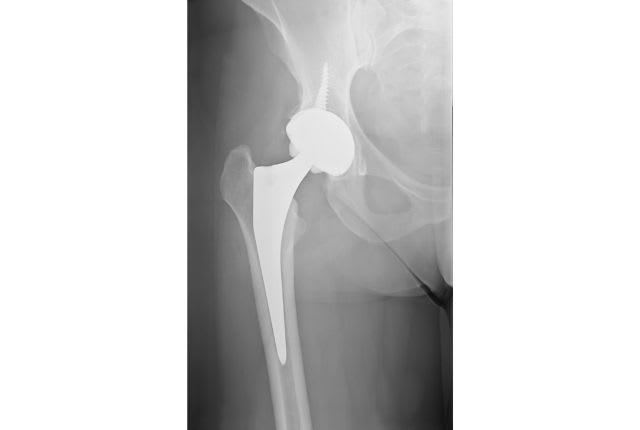

En fonction des matériaux utilisés et du type de fixation réalisée, il existe plusieurs types de prothèses totales de hanche. La prothèse totale de hanche se compose de trois parties : la tête fémorale, la tige et le cotyle.

Les pièces utilisées peuvent être fixées via un ciment acrylique, qui est une sorte de résine ; ou les pièces peuvent se fixer d’elles-mêmes, via l’os lui-même. La tête fémorale et le cotyle peuvent être en métal ou en céramique. La partie fixée à l’os coxal peut être aussi en polyéthylène. Les têtes fémorales existent en plusieurs diamètres.

Le chirurgien procède tout d’abord à une incision au niveau de la hanche. Puis il retire les parties endommagées, et la tête du fémur, pour permettre d’insérer une tige entre la tête fémorale artificielle et la cupule, élément fixé au bassin. Les pièces sont fixées naturellement ou par ciment. Les parties sont emboîtées, et un drainage est effectué.